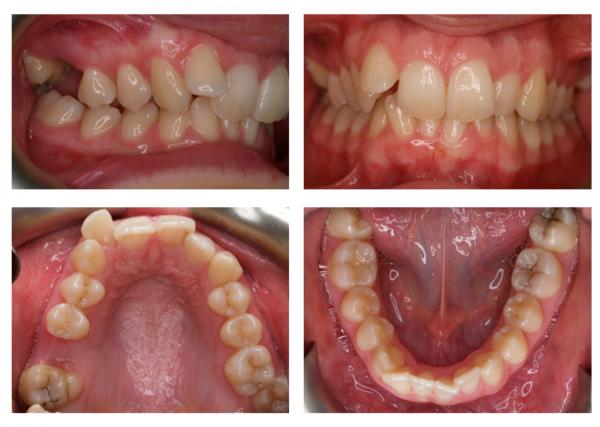

Фото до и после

Фото 2. Слева – фото до процедуры по удалению зуба, справа видны последствия – изменение прикуса.

Фото 3. На фото видны изменения, к которым привели зубы мудрости, при этом остальные начали сдвигаться, торчать в разные стороны.

Фото 4. На фото видно, что нижние зубы мудрости растут в неправильном положении, в такой ситуации один из резцов ушел внутрь челюсти.